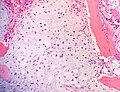

Microscopic findings

- Lobules of uniform to polymorphic densely-packed large cells

- Well defined pushing borders

- Clear to intensively acidophilic granular cytoplasm cytoplasm with vacuoles

- Central nuclei with occasional prominent nucleoli

- Low mitotic rate

- Clear cell areas lack production of hyaline chondroid matrix

- Areas with osteoclast-type giant cells mixed with small trabeculae of reactive bone

- May contain conventional low-grade chondrosarcoma

- May have secondary aneurysmal bone cyst changes